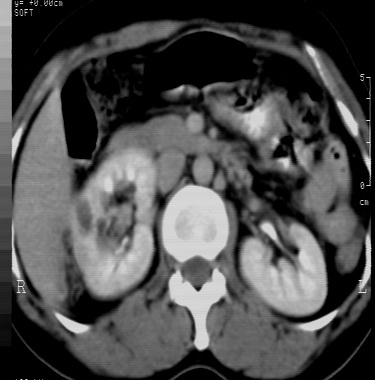

标题: CT24780:女 41岁 右肾多发低密度占位性病灶 [打印本页]

女 41岁 超声检查:右肾多发实质性包块,性质待查(提示:错构瘤或其它病变),临床病史不详。

结果收到---右肾细胞癌;单就影像表现是应该首先考虑血管平滑肌脂肪瘤。

该病理结果应该送高级别医院做病理会诊,否则会影响影像医师今后的判断。免疫组化结果也并未公布,结果非常可疑。应进一步证实。